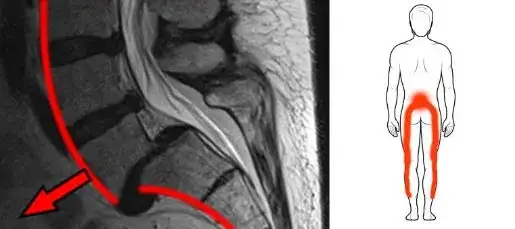

Neurolog jest specjalistą, do którego warto się udać, gdy ból kręgosłupa współwystępuje z objawami neurologicznymi, takimi jak dętwienie, mrowienie czy osłabienie mięśni. Tego typu objawy mogą wskazywać na problemy z układem nerwowym, takie jak rwa kulszowa. Neurolog przeprowadza szczegółowe badania, aby zdiagnozować przyczynę bólu oraz ocenić stan nerwów. W zależności od diagnozy, może zalecić leczenie farmakologiczne, rehabilitację lub dalsze badania, aby wykluczyć poważniejsze schorzenia.